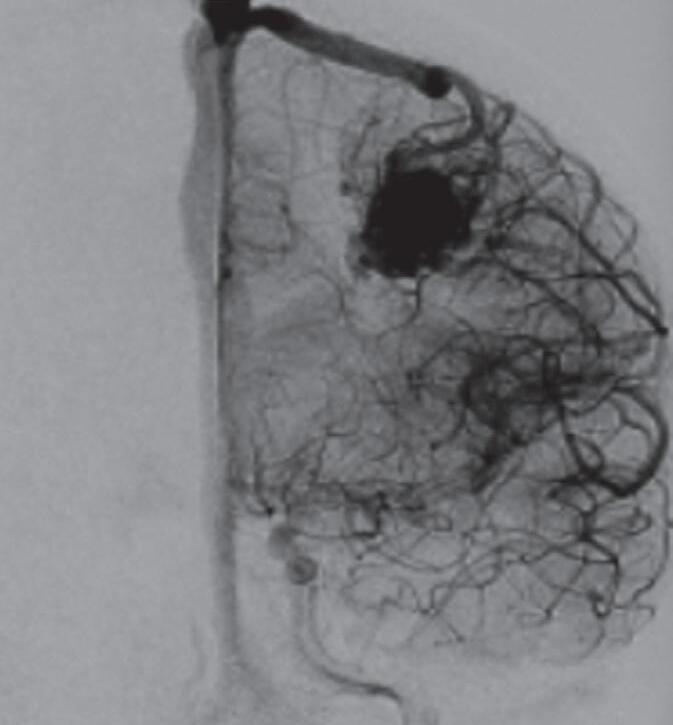

Fig. 1-16. RNM encéfalo T1 com contraste: (a) Coronal e (b) axial demonstrando MAV grau 4 frontoparietal esquerda. (c,d) Arteriografia cerebral AP mostrando a irrigação pelos ramos da cerebral anterior e média esquerda, além da cerebral anterior direita, com drenagem superficial para o seio sagital superior. Seta azul apontando para o nidus da MAV.

A soma dos pontos de cada um desses três critérios resulta em uma pontuação total, que ajuda a determinar a gravidade da MAV e, assim, a abordagem terapêutica a ser instituída. Cada grupo da classificação de Spetzler-Martin demonstra graus variáveis de risco e complexidade, com implicações diretas na escolha do tratamento. A seguir, exemplos de cada um dos cinco graus desta classificação: grau 1 (Fig. 1-13), grau 2 (Fig. 1-14), grau 3 (Fig. 1-15), grau 4 (Fig. 1-16), grau 5 (Fig. 1-17). A classificação de EM pode gerar uma combinação de resultados e ser utilizada para nortear o tratamento. Apesar de ter sido, na época, um grande avanço na avaliação e no tratamento das MAVs cerebrais, a classificação de Spetzler-Martin necessitou ser modificada, em virtude dos avanços no diagnóstico e no tratamento dessas lesões. Em 2010, Lawton propôs essa mudança objetivando facilitar mais ainda a tomada de decisão terapêutica das MAVs.28 Assim, o novo sistema possibilita uma melhor análise do padrão de drenagem venosa, por exemplo. Então, com base nesse critério, malformações de pequeno tamanho localizadas em áreas não eloquentes, com drenagem venosa profunda, são mais complexas de tratar do que as MAVs grandes, localizadas em áreas eloquentes, porém sem comprometimento da drenagem venosa ou que apresentem um sistema de drenagem